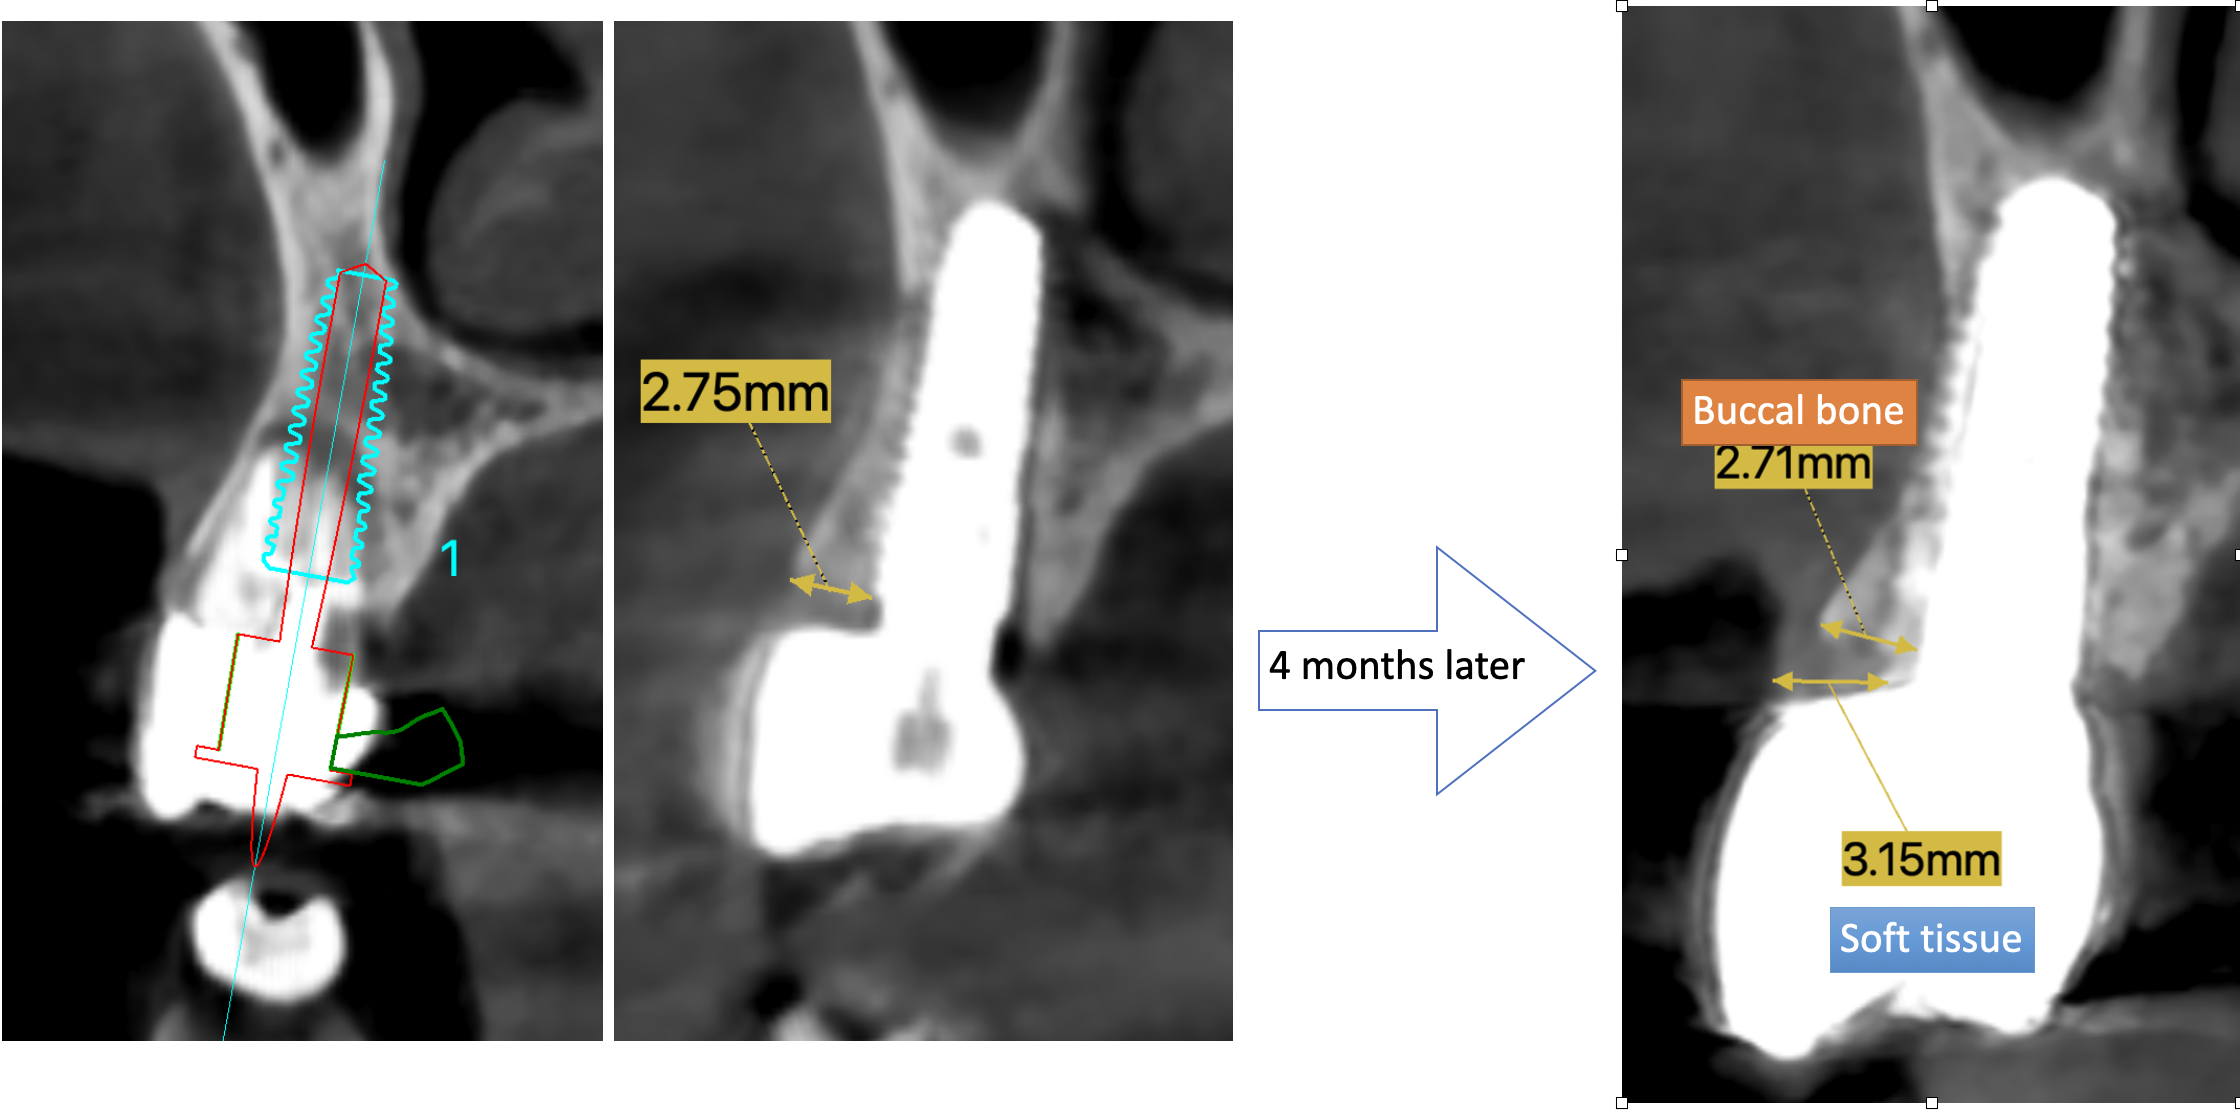

Each case is documented with clinical pictures before, after and during operation. For most of the cases there is surgical video. CBCT before, in the OP day and 4 months after, or longer period of time will demonstrate the volume of buccal bone and soft tissue. Depends of time available, between 13 and 20 clinical cases can be shown.